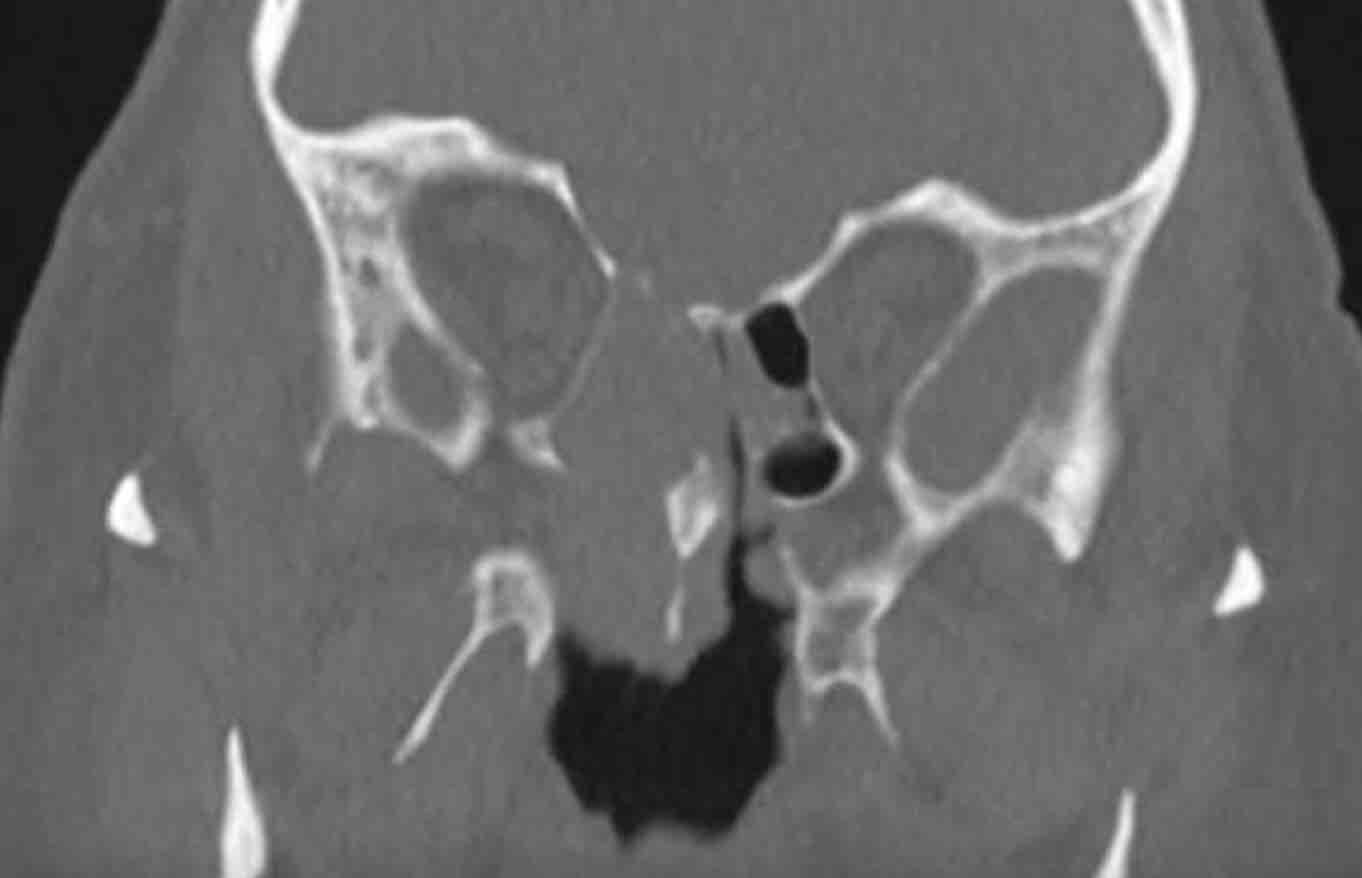

Các hình ảnh này của bệnh nhân nam 47 tuổi, có triệu chứng căng tức vùng trán.

Hãy quan sát các hình ảnh trước.

Dấu hiệu hình ảnh:

- Tổn thương giãn rộng đẩy nhãn cầu trái sang bên.

- Tổn thương có bờ rõ nét.

- Tổn thương xuất phát từ xoang trán trái.

- Thành trong hốc mắt trái (đầu mũi tên đen) và nền sọ (đầu mũi tên trắng) bị mỏng đi, nhưng không có phá hủy xương.

MRI được thực hiện để xác nhận chẩn đoán nhiều khả năng nhất là nang nhầy…

MRI cho thấy tổn thương giãn rộng chỉ có ngấm thuốc tương phản từ ở vùng viền ngoại vi.

Không có ngấm thuốc bên trong tổn thương.

Điều này xác nhận chẩn đoán nang nhầy.

Nang nhầy là tổn thương dạng nang chứa đầy chất nhầy.

Nang hình thành khi lỗ thông của (một phần) xoang cạnh mũi bị tắc nghẽn.